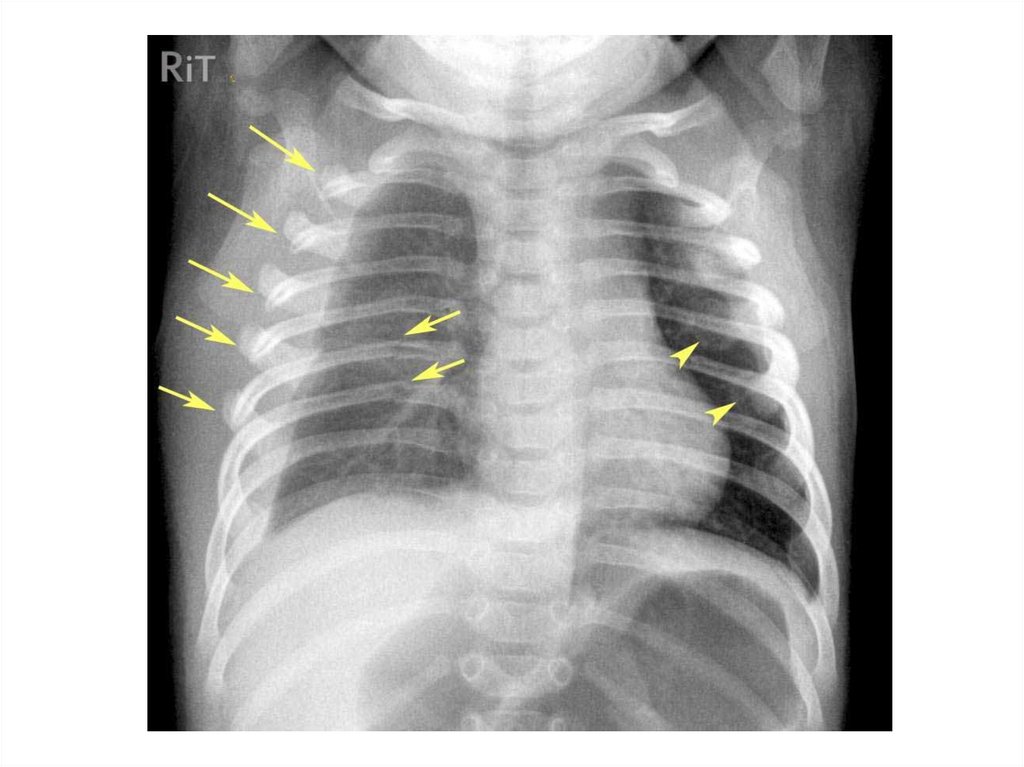

Назовите

• Вид исследования

• Область исследования

• Патологию